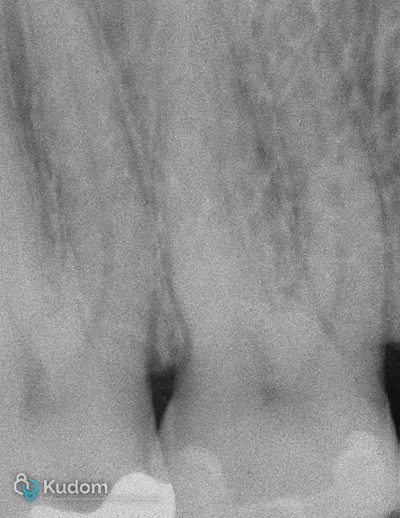

Ritrattamento endodontico complesso di un primo molare inferiore con lesione alla forcazione e otturazione di un canale laterale con successivo build-up per overlay a ricopertura cuspidale.